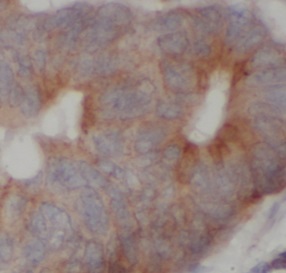

| 验证图片 | Immunohistochemistry of paraffin-embedded human colon cancer tissue slide using FNab10065(HDAC10 Antibody) at dilution of 1:200 |